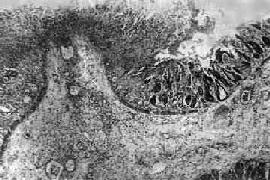

图18-22 细菌性痢疾

结肠粘膜表层坏死并有白细胞和纤维素性渗出物